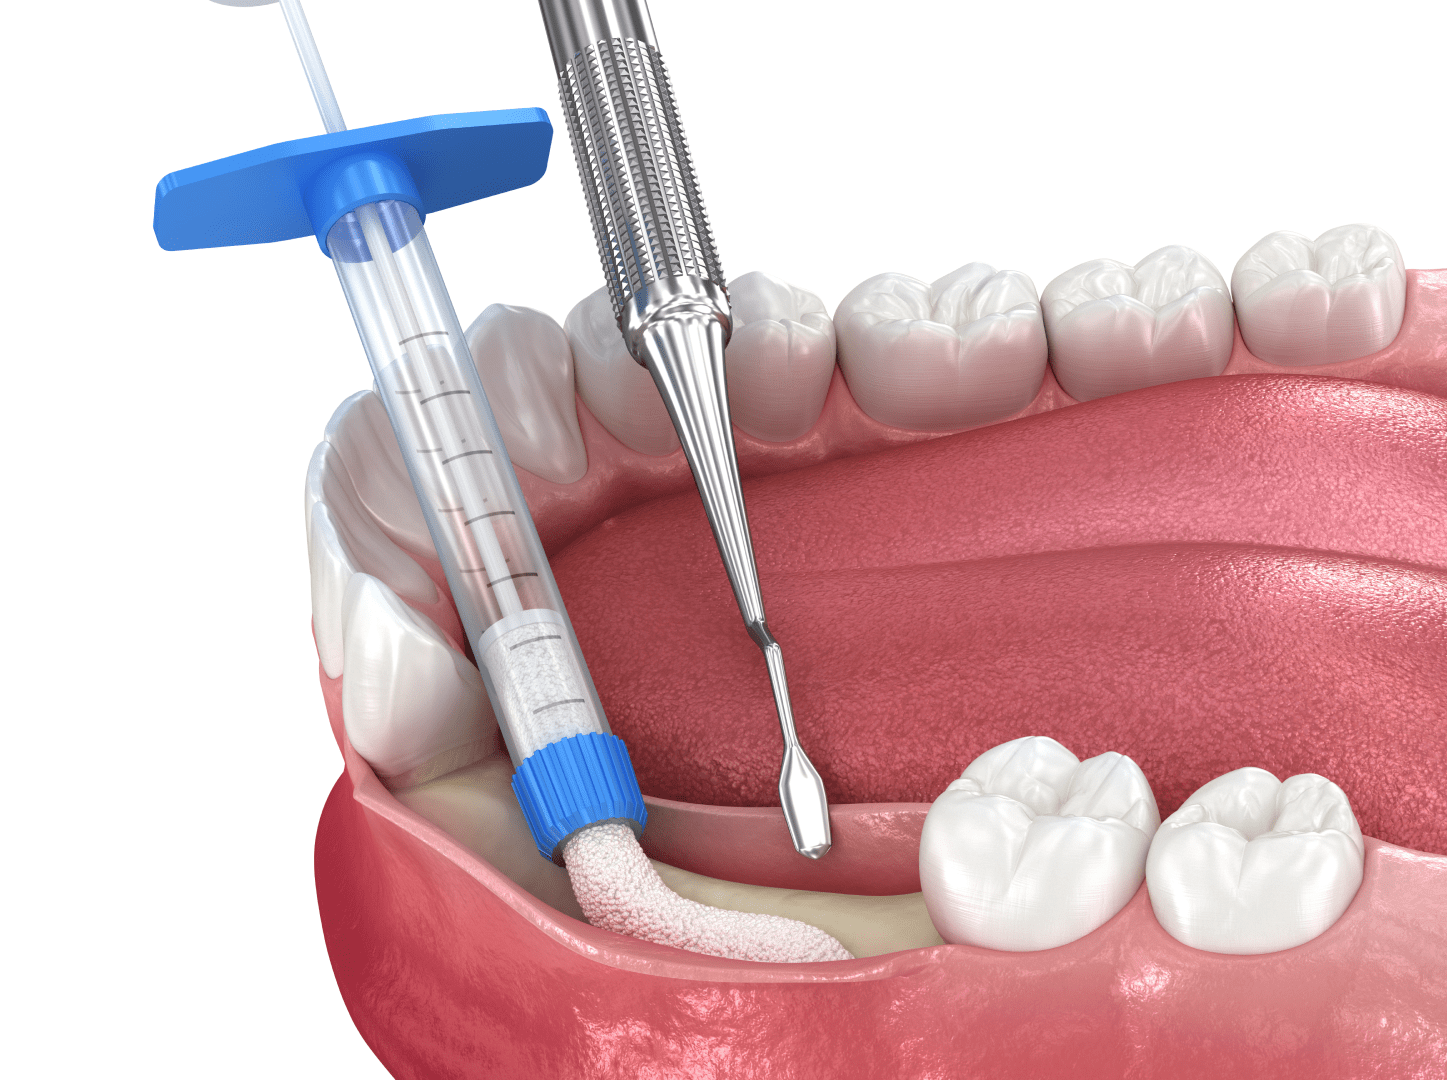

Нарощування кісткової тканини

Іноді підготовка до імплантації потребує проведення синус-ліфтінга. Це процедура з нарощування щелепної кістки. Одна з ключових умов для якісної імплантації — це достатній об’єм кістки, щоб імплант міцно і надовго в ній прижився.

За деяких станів та захворюваннях у пацієнтів відбувається атрофія кістки – поступова її деградація. Така кістка стає тонкою і крихкою, через що ставити туди імпланти не можна. Атрофія виникає при недостатньому навантаженні не щелепу, наприклад після втрати зубів, якщо вони довго були відсутні. Такі проблеми виникають при травмах обличчя, генералізованих формах пародонтиту, а також при остеопорозі2.